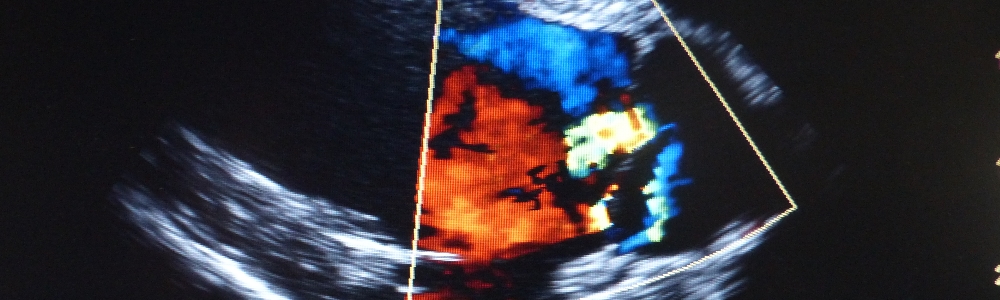

Ultraschallbild

• Herzultraschall mit Doppler EKG